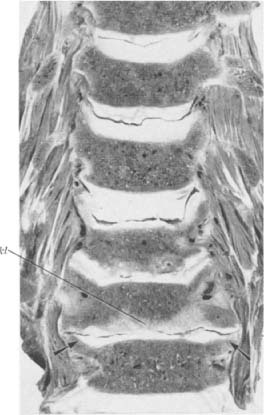

Halswirbelsäule eines 74jährigen Mannes. Bei der untersten Halsbandscheibe sind die Processus uncinati bis zur Horizontalen niedergelegt (Pfeile). Eine dünne Schicht von Faserknorpel vermag die Stöße nicht genügend zu dämpfen: Es kommt zu Sklerosierung nicht im Uncovertebralbereich, sondern in der ganzen Ausdehnung der Knochenendplatte (Skl)